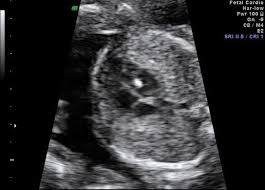

anne karnındaki bebeğin kalp atışı kaç olmalı

anne karnındaki bebeğin kalp atışı kaç olmalı.

anne karnindaki bebegin kalbinde parlaklik nedenleri ve tedavisi